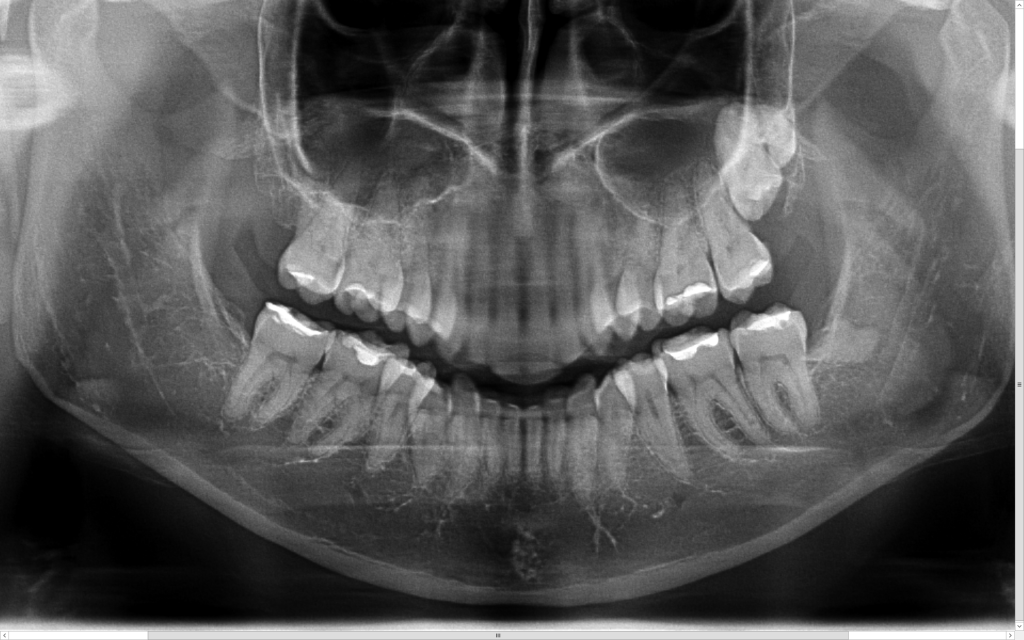

Z uwagi na moją specjalizację kierowani są do mnie pacjenci z tzw. zębami mądrości – ósemkami, które ze względu na ułożenie w kości wymagają operacyjnego usunięcia. Zdarzają się również pacjenci z mezjodensami (fot. 1,2) zębami nadliczbowymi np. dziewiątkami (fot.3), zębami zatrzymanymi (fot 4.), lub zębami zrośniętymi (fot. 5,6). Stomatolog z długą praktyką nie raz w swojej karierze zetknął się z takimi przypadkami.